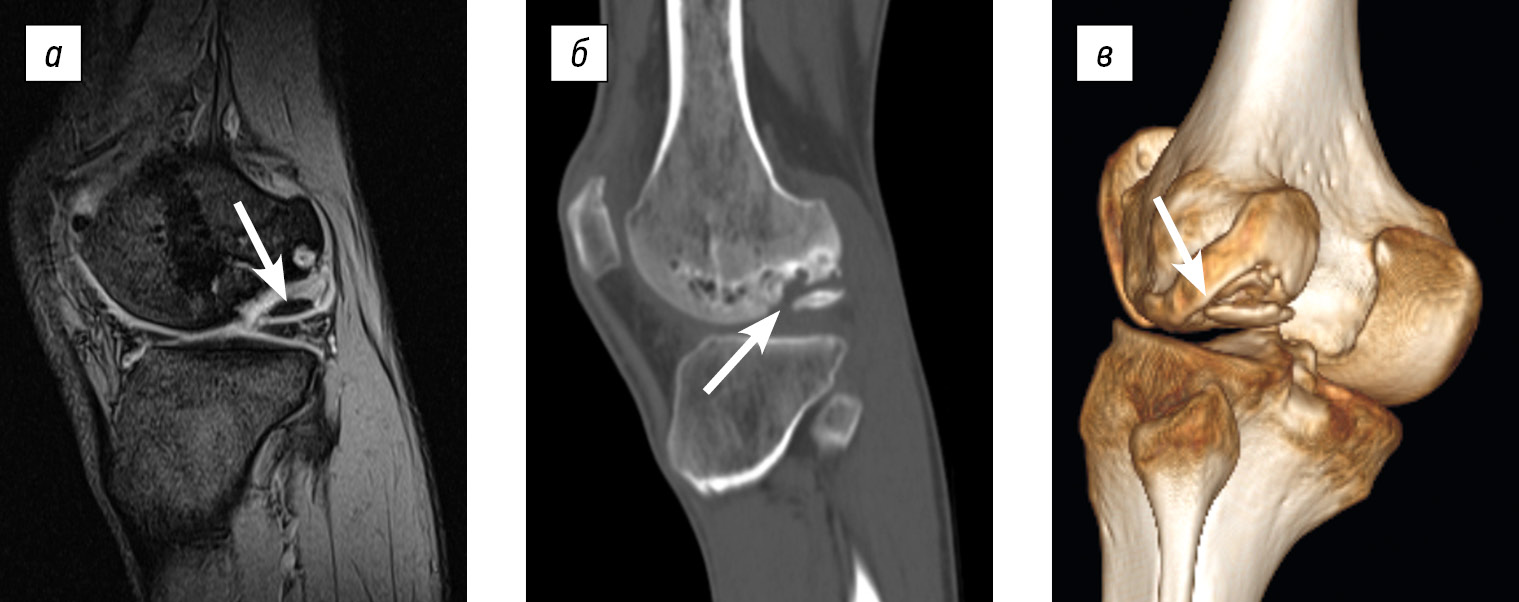

Imaging examinations revealed an osteochondral destruction zone in the lateral condyle of the left femur measuring 3.3 × 2.8 × 1.5 cm, along with a loose osteochondral body measuring 2.2 × 2 × 0.5 cm (ICRS grade IV). The imaging findings are shown in Figure 5.

Fig. 5. Imaging of patient M.: a, magnetic resonance imaging, sagittal slice; b, spiral computed tomography, sagittal slice through the osteochondral defect of the lateral femoral condyle; c, spiral computed tomography, 3D reconstruction illustrating the size of the defect and the presence of a loose osteochondral fragment in the lateral femoral condyle. Arrows indicate the osteochondral defect region and the loose osteochondral fragment.